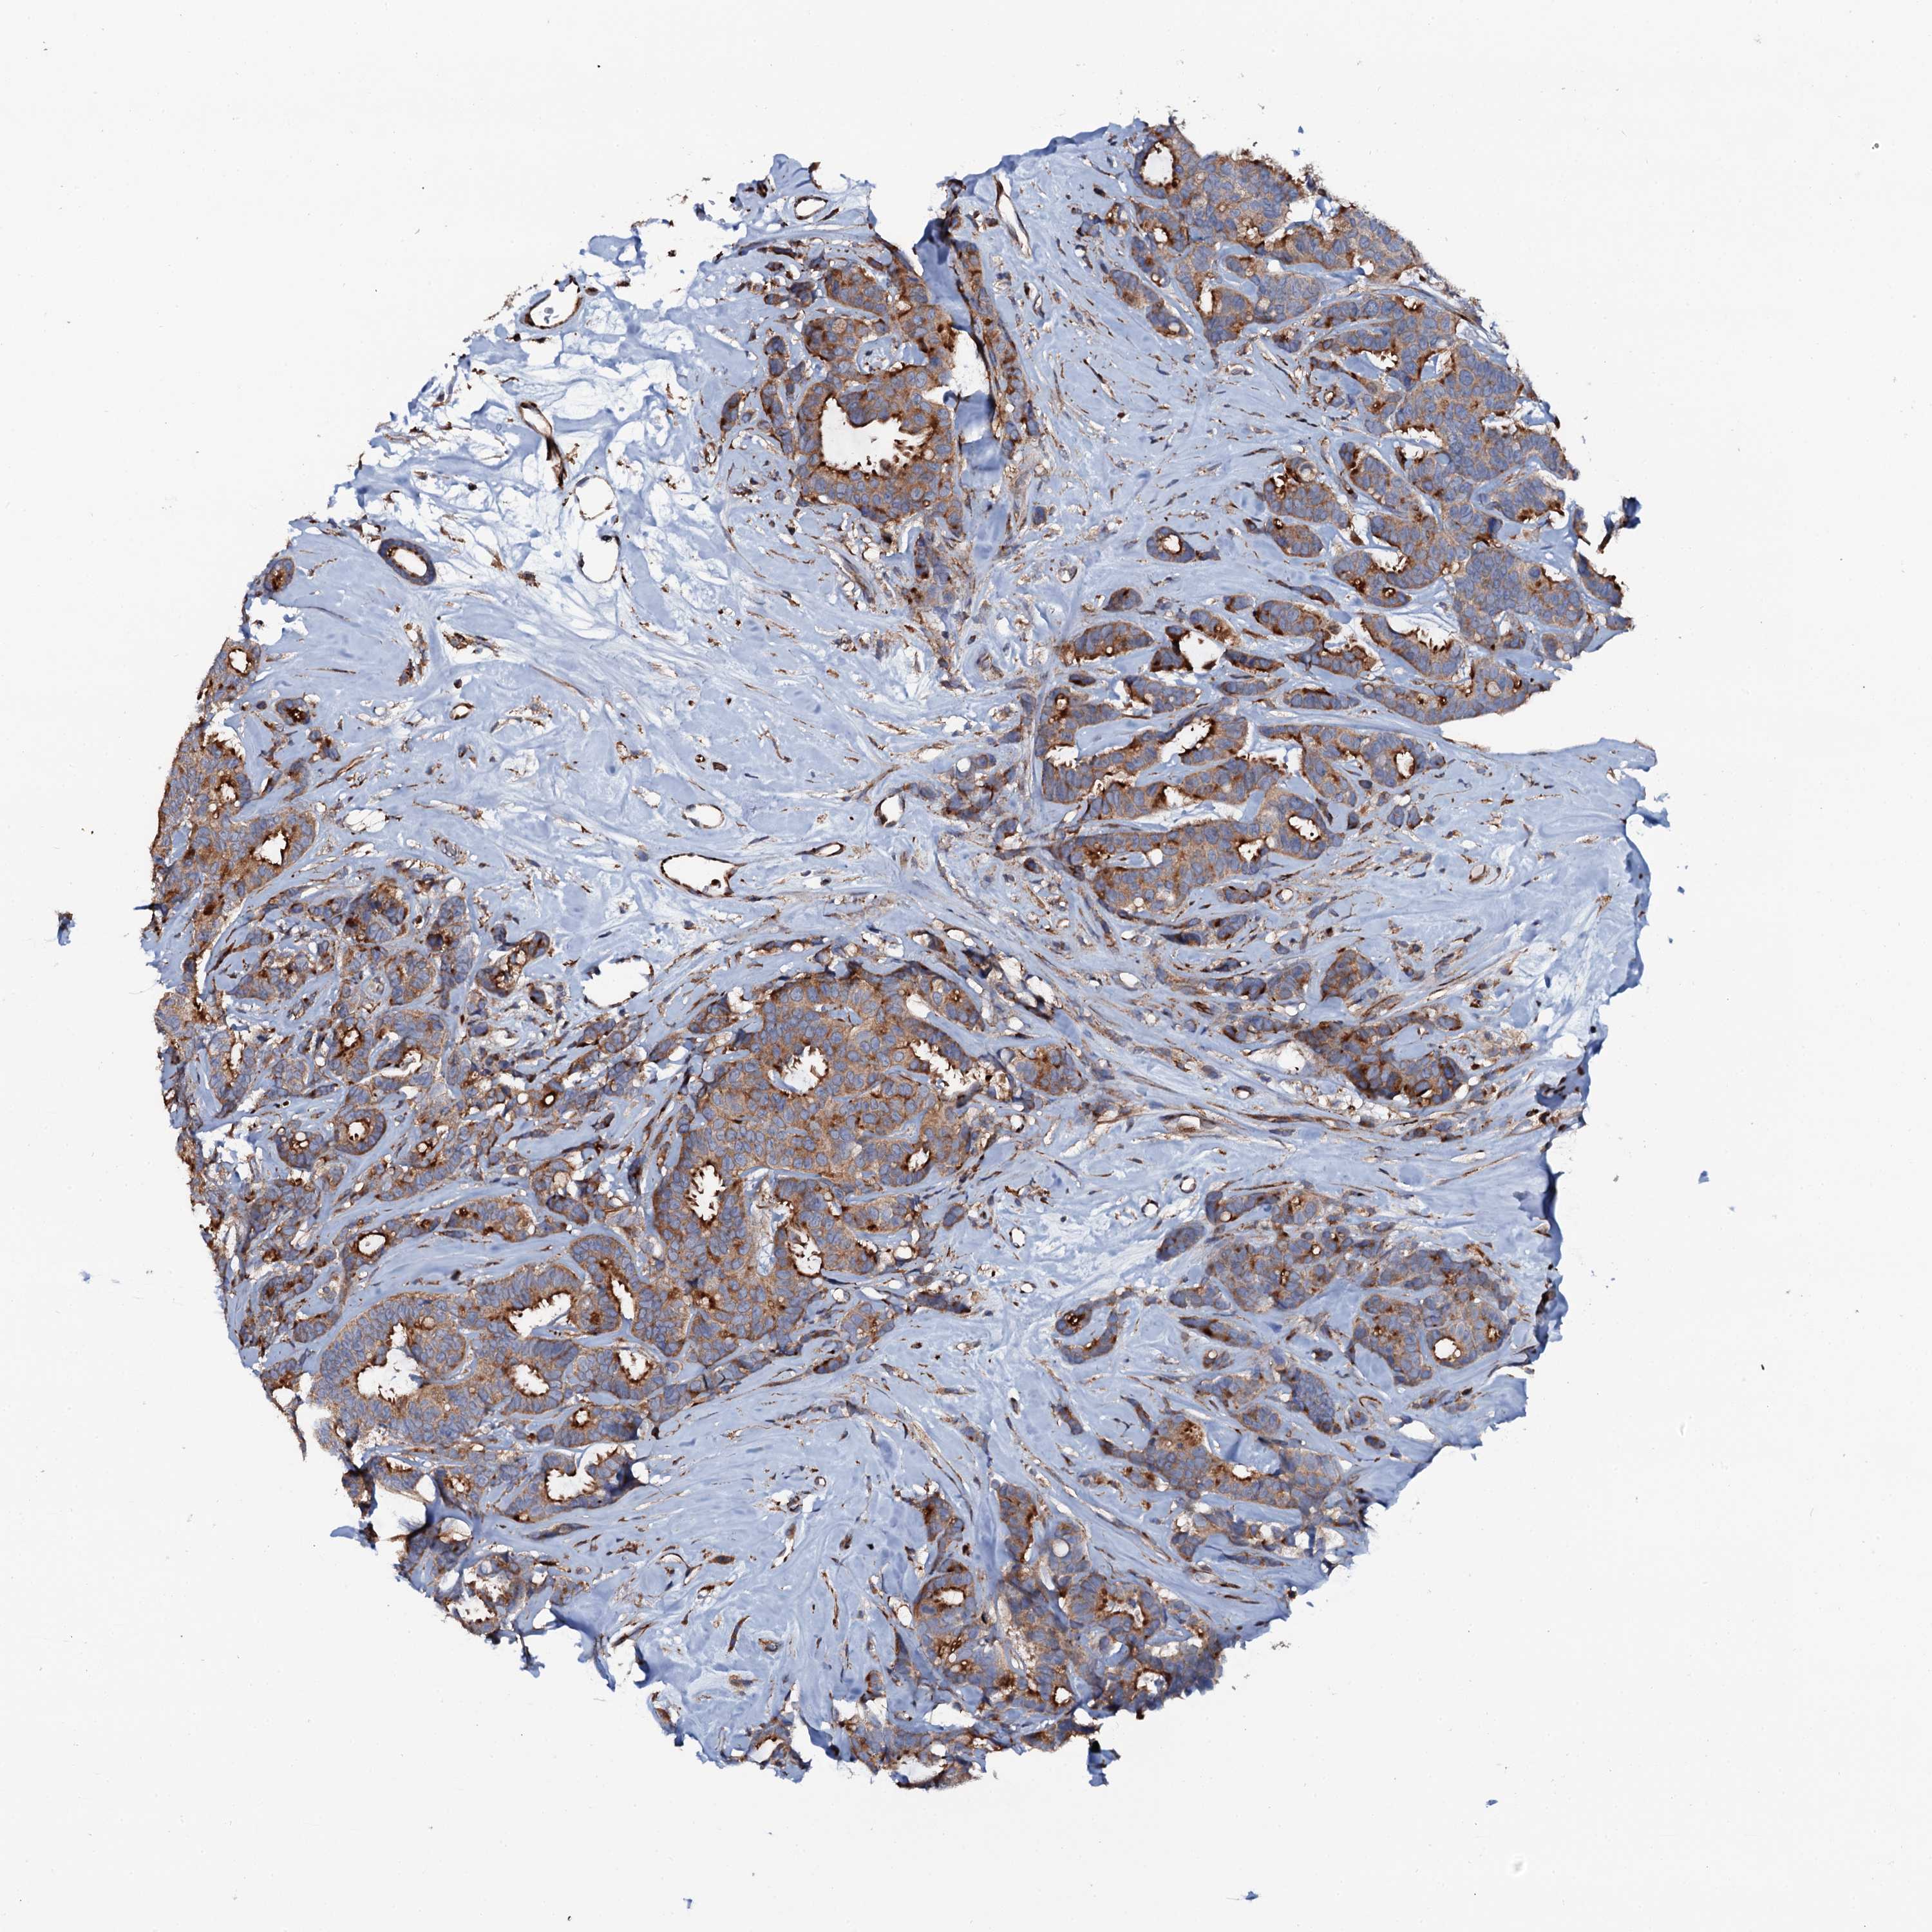

CANCER BREAST CANCER Show tissue menu

BRCA TCGA BRCA VALIDATION PROTEIN EXPRESSION

Breast cancer

Human cancer

VAMP8 is not prognostic in Breast Invasive Carcinoma (TCGA)